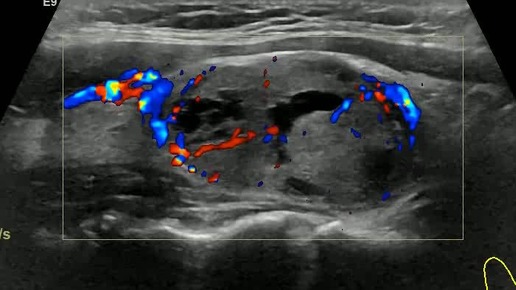

Видео к статье "Стратификация узлов щитовидной железы. TI-RADS-4" https://dzen.ru/a/ZwNx-uQp-Sfk6L46

Ультразвуковые находки от врача УЗД Зорина Я.П.